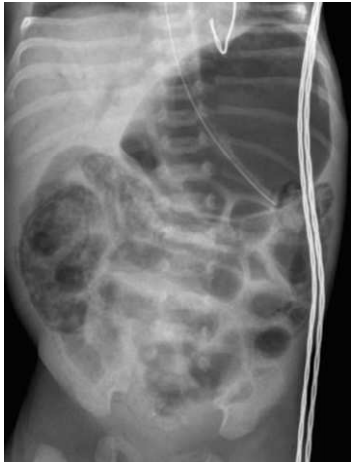

A enterocolite necrosante (NEC), mostrada na figura abaixo, é uma doença de origem desconhecida que afeta principalmente recém-nascidos prematuros (80% dos casos). As manifestações cobrem amplo espectro, de distensão abdominal leve com hematoquezia a choque séptico fulminante com necrose transmural de todo o trato gastrointestinal. Com relação a essa patologia, analise as afirmativas a seguir.

http://www.adhb.govt.nz/newborn/TeachingResources/Radiology/AXR/NEC/NECwithPortalGasAP1.jpg

1) Ocorre tipicamente em recém-nascidos com uma idade gestacional corrigida de 30-32 semanas, um momento em que a maioria dos prematuros está em progressão de dieta enteral.

2) O leite materno pode reduzir o risco de NEC. Uma das ações seria favorecer o crescimento de Lactobacillus bifidus, promovendo o desenvolvimento de um microbioma intestinal saudável.

3) O estagiamento da NEC é realizado com base em sinais sistêmicos e radiológicos.

4) O tratamento deve ser conservador, apenas com vigilância rigorosa e antibioticoterapia nos casos de pneumoperitônio, devido à instabilidade clínica e a gravidade do paciente.

5) A ausência de NEC intrauterina sugere uma necessidade absoluta de colonização intestinal em sua patogênese.

Estão CORRETAS: